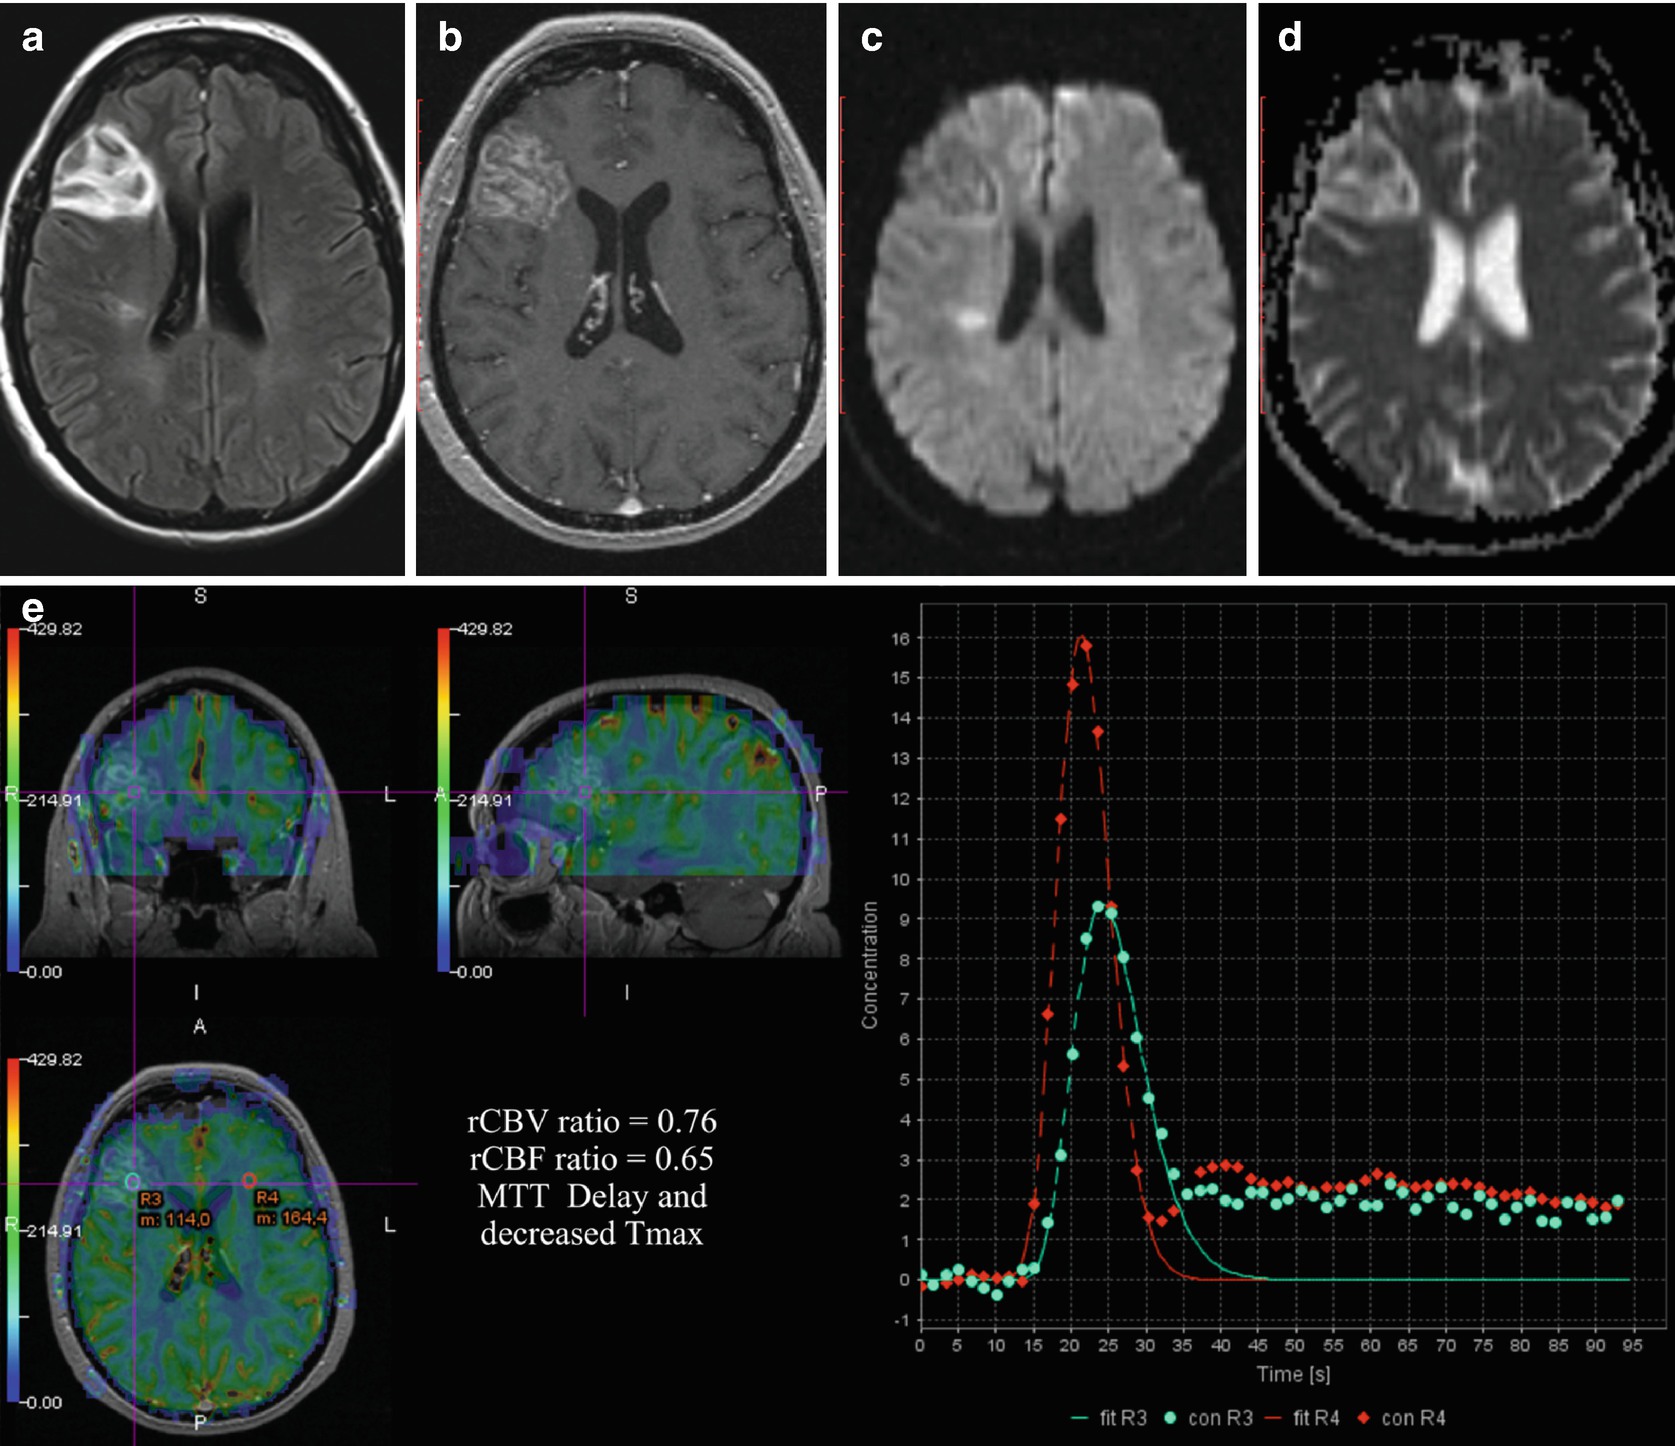

Ct Perfusion In Acute Lacunar Stroke Detection Capabilities Based On Infarct Location American Journal Of Neuroradiology

Frontiers Examining Subcortical Infarcts In The Era Of Acute Multimodality Ct Imaging Neurology